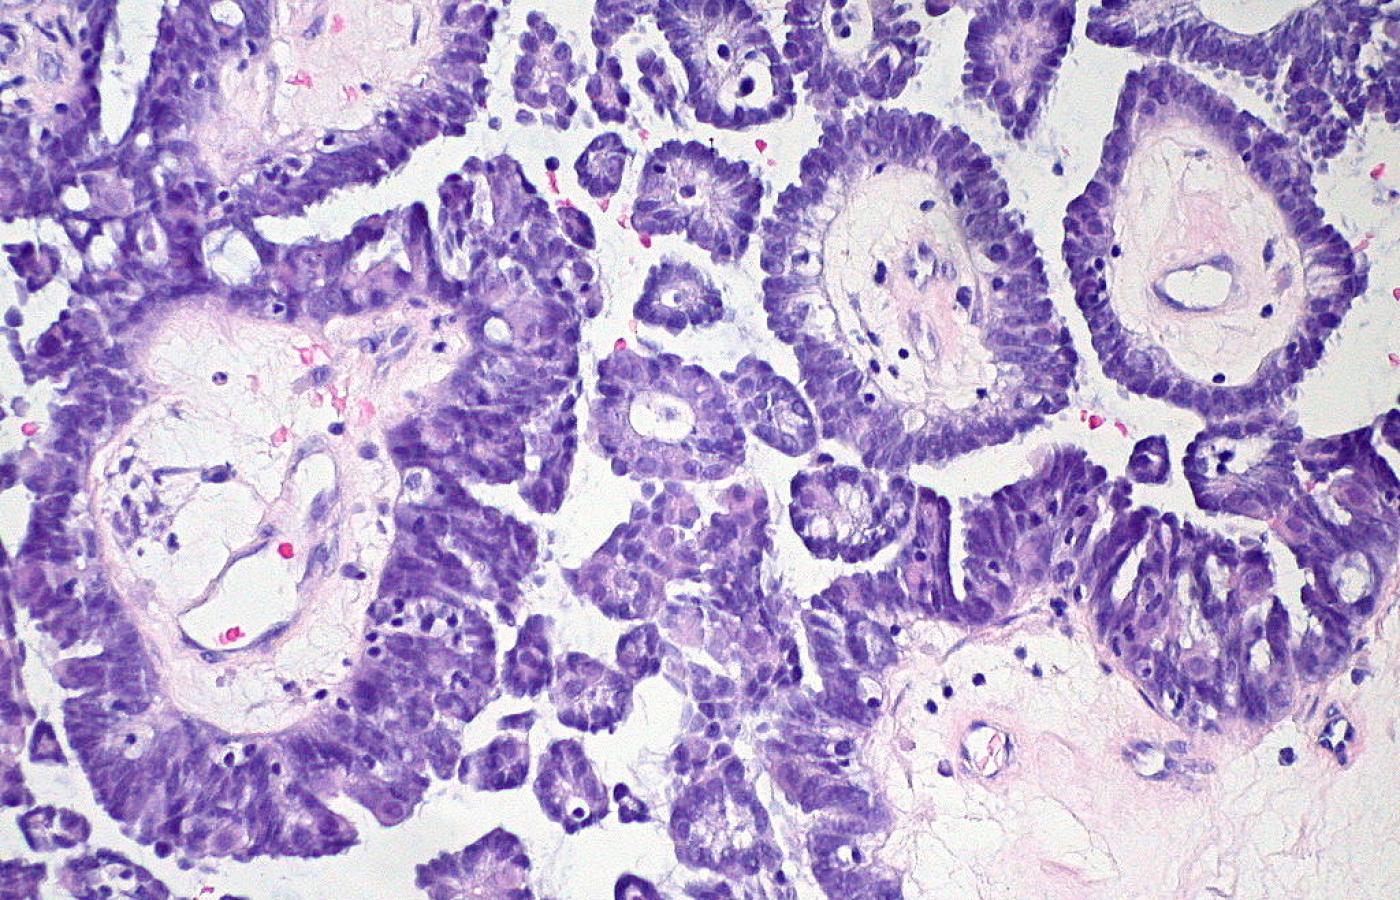

Ed Uthman / Flickr CC by 2.0